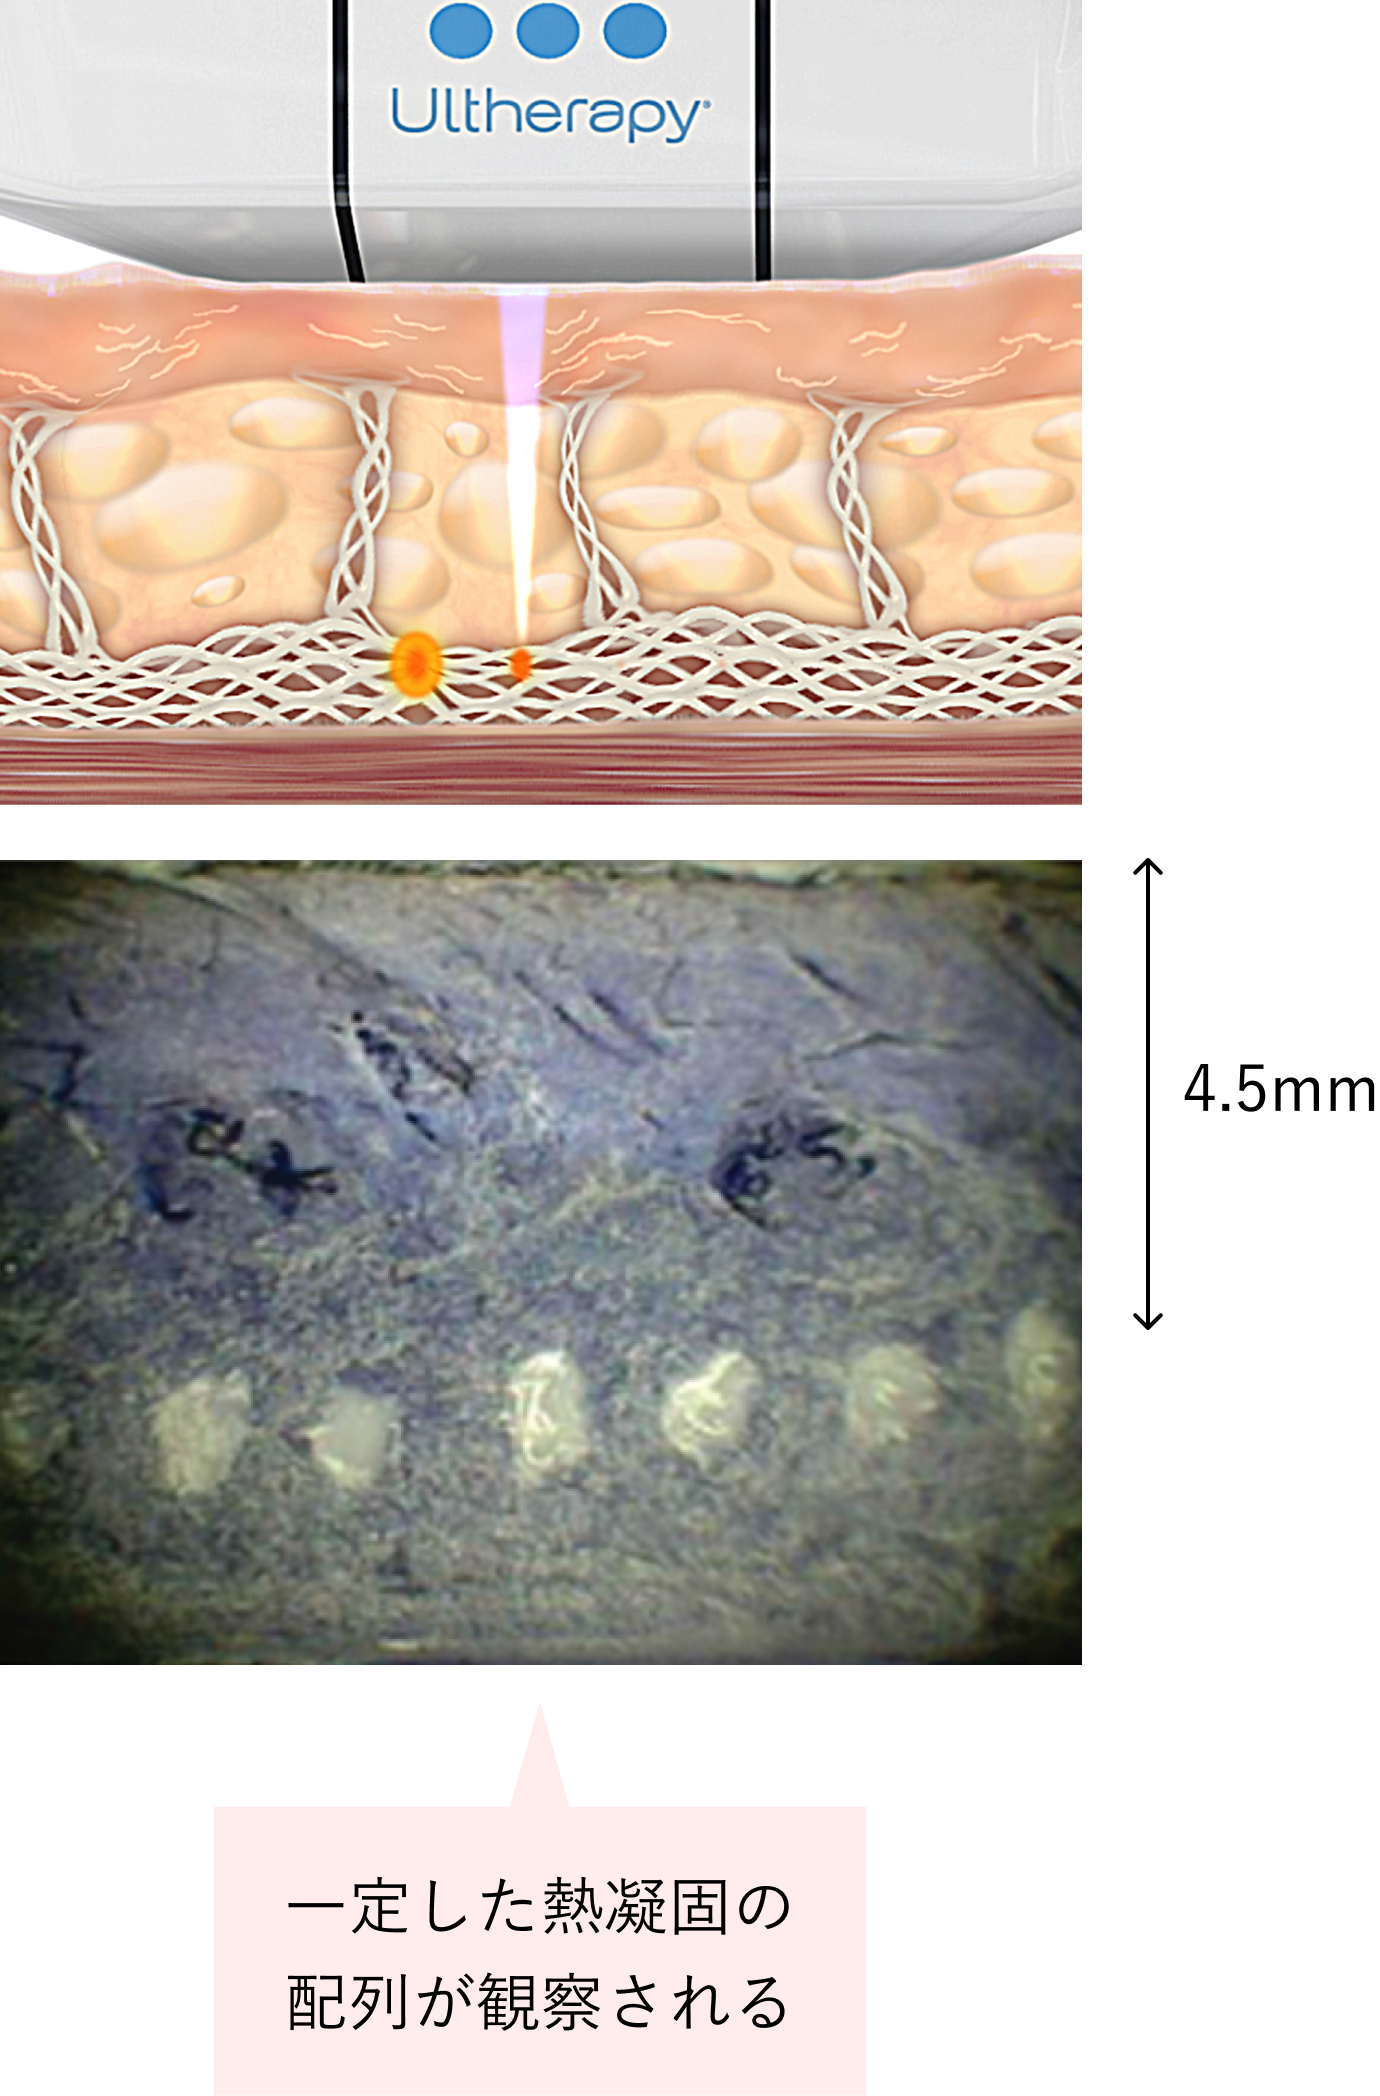

「ウルセラリフト」の均一、かつ正確な熱凝固点

ウルセラリフトは、専用のトランスデューサーによって、約 1mm3の熱凝固点(TCP:Thermal Coagulation Points)を25mmのライン上に均一な間隔で形成していきます。まわりに正常組織を残すことで、痛みや副作用のリスクを抑え、スムーズな創傷治癒反応を促します。

ウルセラリフトは、非侵襲でありながら、これまでのアプローチでは難しかったSMAS筋層へ正確に熱凝固点を形成し、リスクを最小限におさえながら確実にリフトアップ効果を実現します。 類似品が数多く出ていますが、他社製品と比較しても、熱凝固点形成の均一、かつ正確さは、一目瞭然です。

ウルセラリフトの照射図

*人間の組織に近い素材を使用

ウルセラリフト 照射イメージ